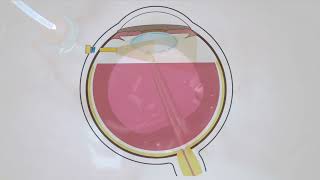

Heads up 3D video in a cataract surgery and vitrectomy What is a vitrectomy? (3D Animation)

How long will it take to get clear vision after cataract surgery? | OCL Vision 3D heads-up surgery for MICS and MIGSs - Supplementary video [ID 227318]

Cataract surgery in the presence of dense vitreous opacities Macular Detachment – Vitrectomy and Iluvien Fighting – A NGENUITY 3D Capture by Bernardete Pessoa, J

Macular Detachment – Vitrectomy and Iluvien Fighting – A NGENUITY 3D Capture by Bernardete Pessoa, J